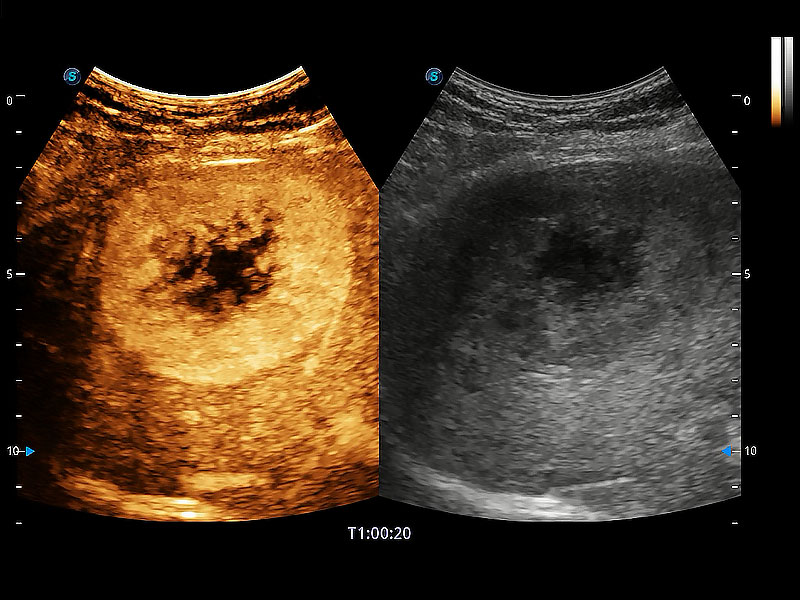

极大提升超低速微细血流的检出能力,同时更精准地滤除软组织和超声信号,为兽用医生提供以往无法通过常规血流获得的疾病诊断信息。